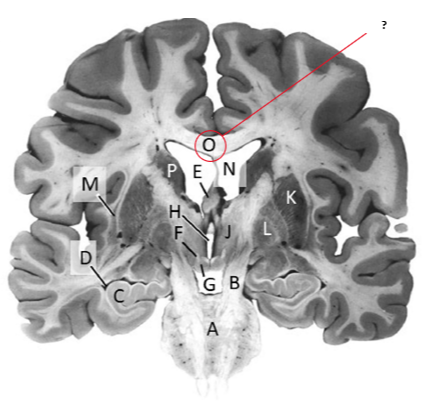

Name this and state its function.

Corpus Callosum.

Name and state its function.

Lateral ventricles.

Name.

Temporal horn of lateral ventricle.

Name this, state its function and consequence of lesion in this area.

Fornix.

Transmits Theta waves aswell.

Lesion: anterograde amnesia.